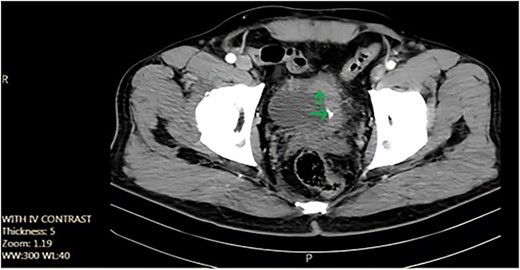

We report the case of a 52-year-old non-smoker, non-addicted male with a past surgical history of cystolithotomy 30 years ago and no comorbidities. The patient presented to our center with painless gross hematuria without any obstructive or irritative urinary signs or symptoms. Initial ultrasonography revealed an 18 × 9 mm bladder stone, for which the patient was referred for cystolitholapaxy. Subsequent follow-up with ultrasonography and abdominopelvic computed tomography (CT) scan identified a 45 × 25 mm triangle laminated bladder stone (Fig. 1).

Axial pelvic CT scan shows large urinary bladder tumor (arrow).